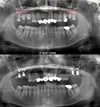

تطبيقات الزركونيوم

تطبيقات البورسلين

فينير اللومنات